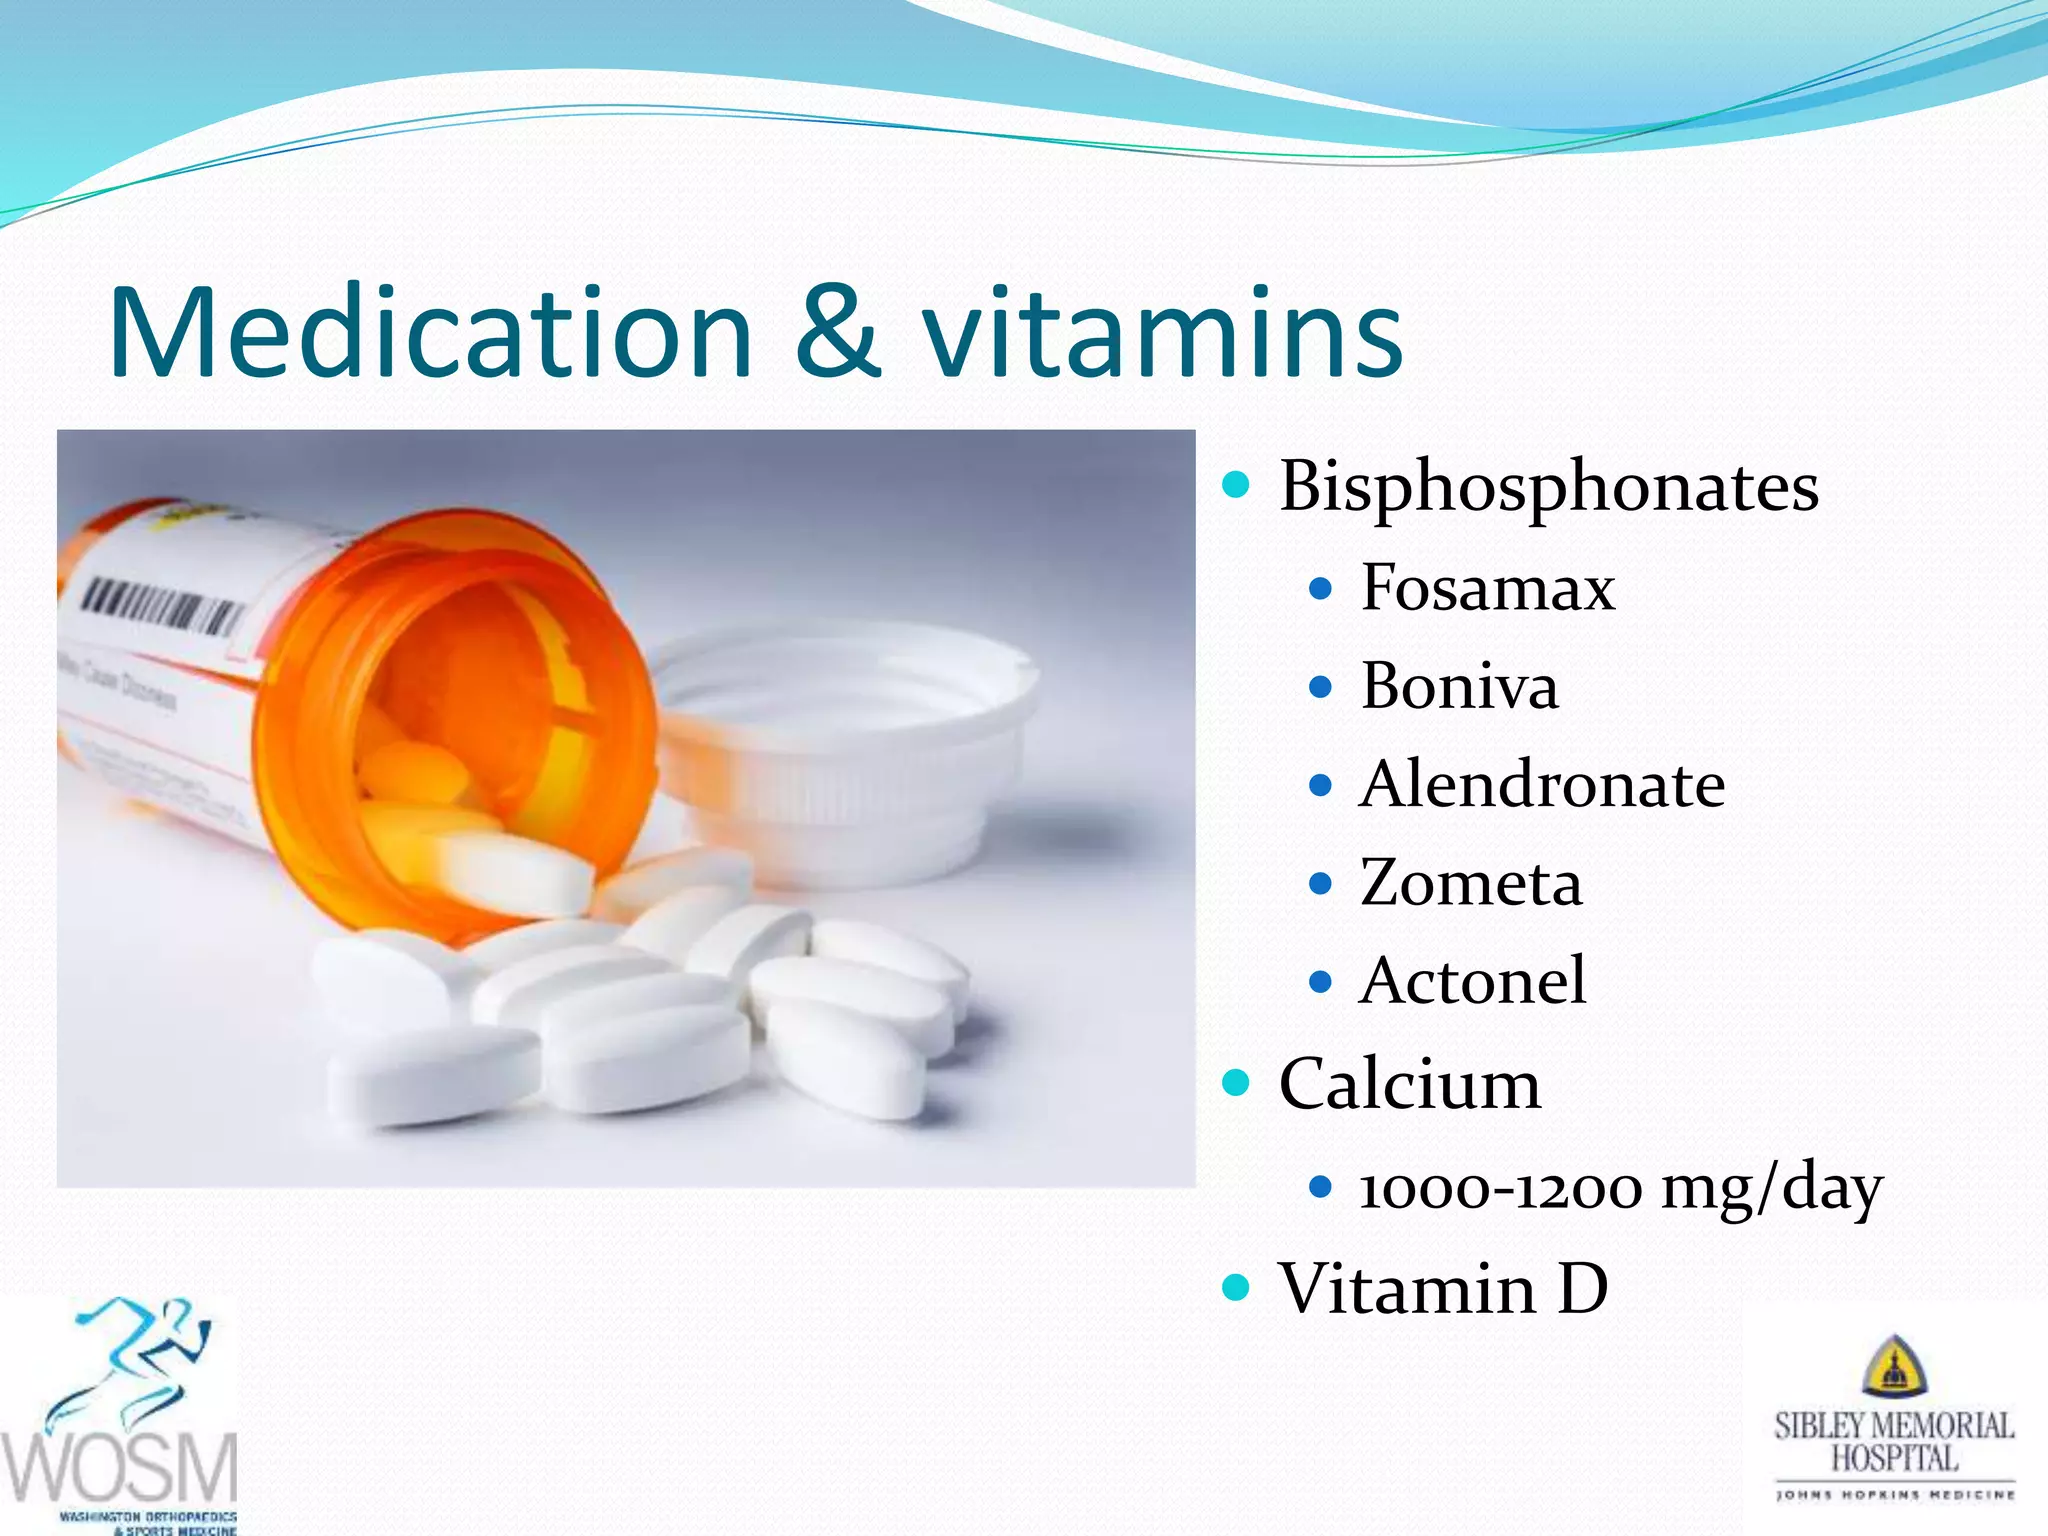

This document discusses wrist fractures, including who is most at risk, common causes, signs and symptoms, treatment options, and prevention. The elderly and those with osteoporosis are most prone to wrist fractures due to falls. Treatment may involve splinting, casting, closed reduction, or surgery depending on the fracture. Maintaining bone health through medication, vitamins, exercise, and diet can help prevent wrist fractures.